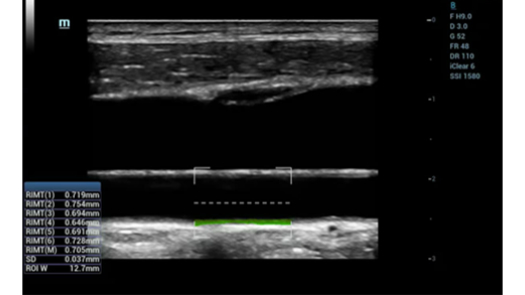

Pencitraan Tepercaya

MX7, berdasarkan platform ZST + revolusioner kami, teknologi probe premium, dan algoritme canggih, dirancang untuk memberikan pencitraan tepercaya bagi dokter, memberikan lebih banyak kepercayaan pada diagnosis.